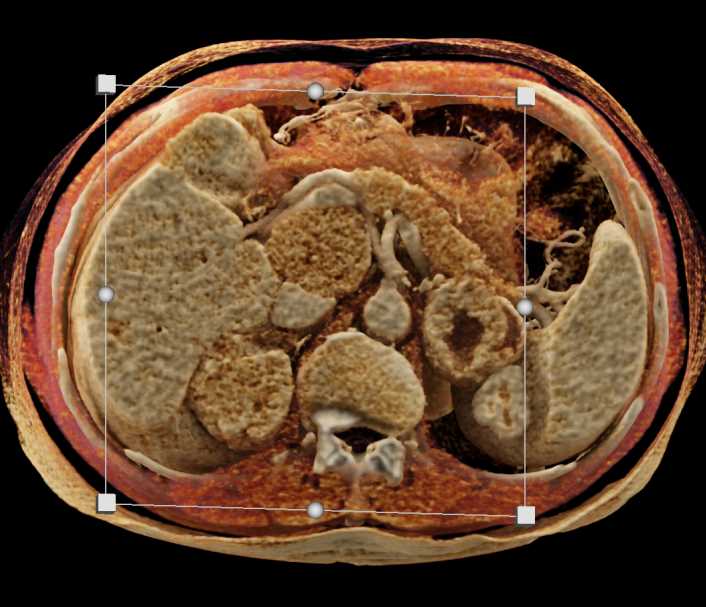

Left Adrenal Metastases from Renal Cell Carcinoma